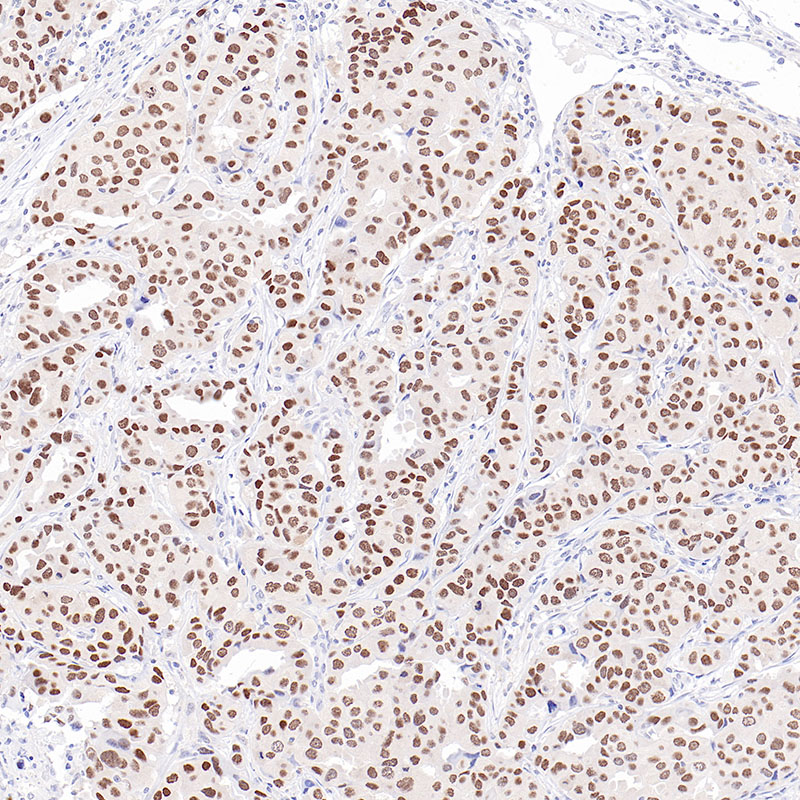

Immunohistochemistry analysis of paraffin-embedded Breast Cancer using TRPS1 antibody.High-pressure and temperature Tris-EDTA pH 8.0 was used for antigen retrieval.